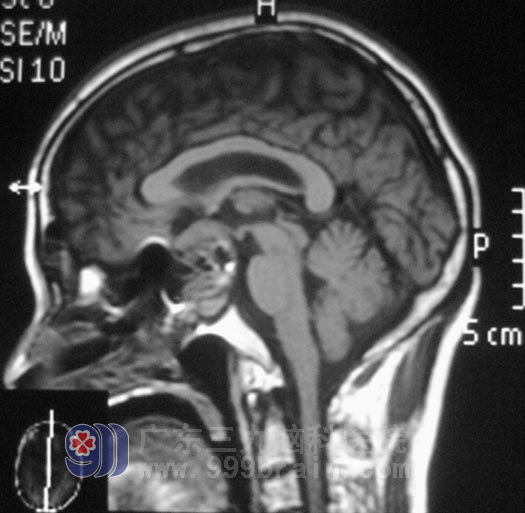

两周前,曾先生的视力下降较前明显,并伴有间断头痛,医生建议行脑部检查,头颅MR报告显示:鞍区占位性病变,考虑垂体大腺瘤,大小约28mm×27mm×30mm:

5月3日,曾先生在全麻下行经鼻蝶垂体瘤切除术,术前导航定位,术中显微镜下见肿瘤呈灰白色,质软,镜下予肿瘤切除,并修补鞍底。术后,他的视力较前好转,没有出现并发症。术后病理结果为:垂体瘤(促性腺激素分泌腺瘤)。